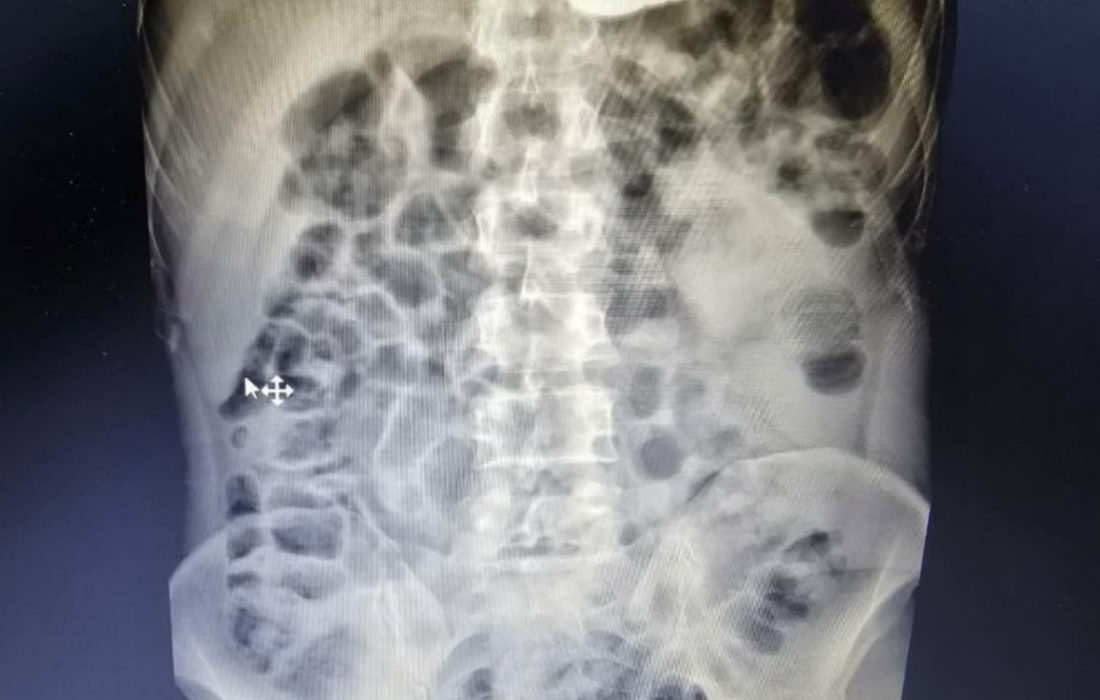

به گزارش خبرگزاری صداو سیما مرکز یزد و به نقل از روابط عمومی بیمارستان ضیایی اردکان، پس از تصویربرداری از بیمار مشخص شد قطعه فلزی شکسته و تیز از دوازدهه عبور کرده و در روده گیر کرده است؛ وضعیتی که معمولاً نیازمند اعزام فوری و جراحی باز است.